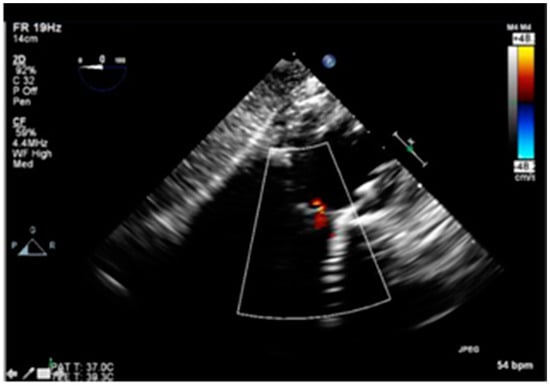

Post valvuloplasty, the patient developed significant acute aortic regurgitation with hemodynamic instability as shown in Figure 3.

Figure 3.

Intraoperative Trans-esophageal echocardiogram showing severe aortic regurgitation.

Tandem Life® support was increased to 4 L per minute. At this point, the Gore dry seal sheath was removed from the right femoral artery, and the 26 mm Medtronic CoreValve EvolutR valve delivery system was introduced via the right femoral artery via its in-line sheath, advanced into position across the valves as shown in Figure 4, and deployed in standard fashion with right ventricular pacing at 100 beats per minute.